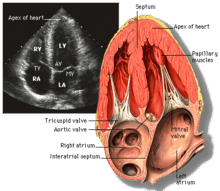

Transthoracic echocardiogram uses ultrasonic waves for continuous heart chamber and blood movement visualization. In recent times, it has become one of the most commonly used tools in diagnosis of heart problems, as it allows non-invasive visualization of the heart and the blood flow through the heart, using a technique known as Doppler.